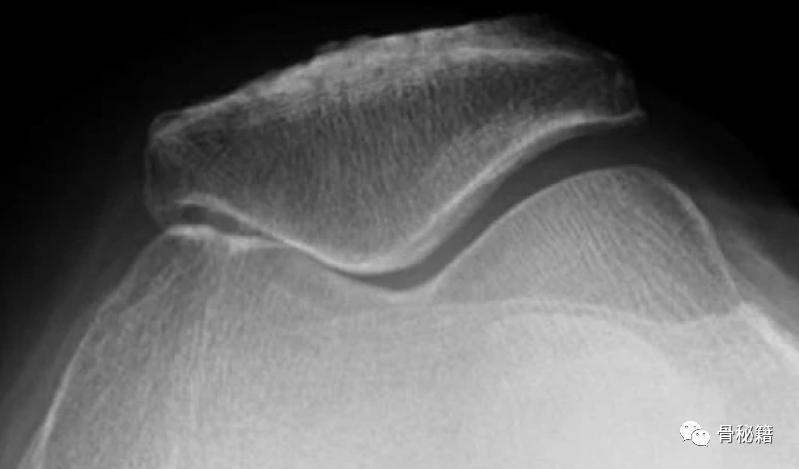

PF 骨关节炎的 Iwano 分类。A I期:关节间隙至少3mm的轻度骨关节炎;B ) II 期:中度骨关节炎,关节间隙 < 3 mm 但无骨接触;C)III期:严重的骨关节炎,骨接触小于关节面的四分之一;D ) IV 期:非常严重的骨关节炎,关节面完全相互接触,通常伴有大的外侧髌骨骨赘,以及外侧髌骨小面的骨质流失